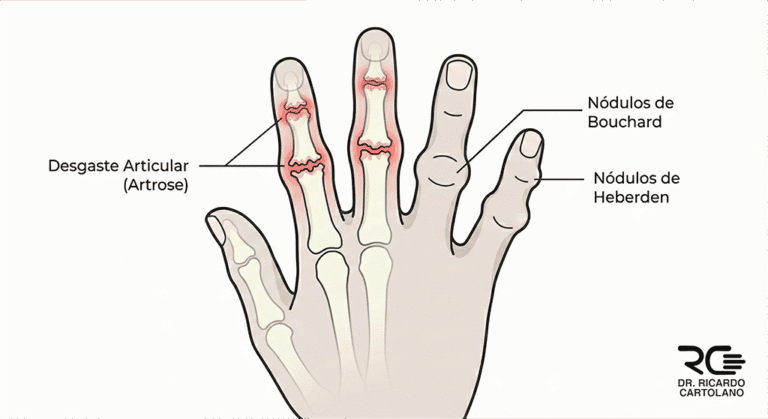

A Artrose (também conhecida como osteoartrite) é o desgaste da cartilagem que reveste as nossas articulações. A cartilagem funciona como uma “almofada” ou uma “capa protetora” lisa, que permite que os ossos deslizem suavemente uns sobre os outros.

Quando essa cartilagem se desgasta e fica fina, os ossos começam a raspar uns nos outros. O corpo reage a esse atrito tentando “consertar” a articulação, o que acaba criando inflamação, dor e os famosos “bicos de papagaio”, que nas mãos aparecem como nódulos duros.

Nódulos (caroços): São o sinal mais visível. Quando aparecem na ponta dos dedos (última articulação), são chamados de Nódulos de Heberden. Quando aparecem no meio dos dedos, são os Nódulos de Bouchard.